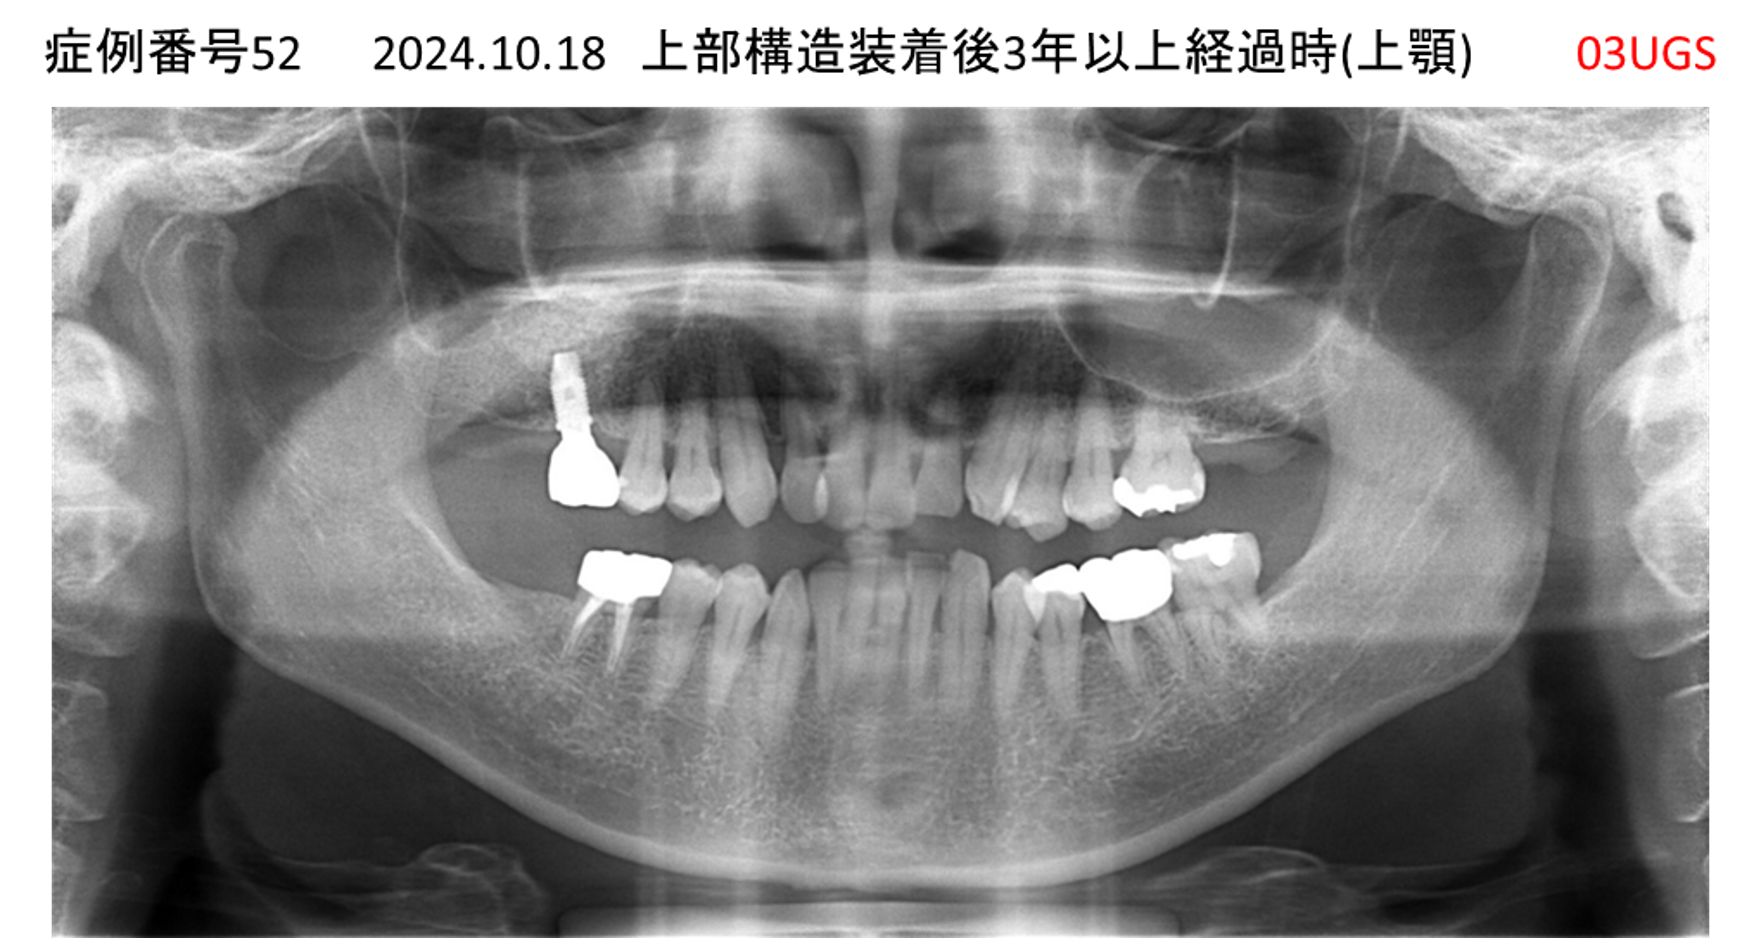

上の前歯が揺れてきてかめない患者様のインプラント症例

| 治療名称 |

インプラント |

| 治療費用 |

440万円+税 |

| 治療期間 |

6か月 |

| 患者さんの症状(主訴) |

上の前歯が揺れてきた。かめない |

| 治療内容 |

サイナスリフト、GBR、インプラント、即時荷重 |

| 治療結果 |

上の前歯の揺れが収まった。奥歯でしっかり噛める。 |

| 治療の注意点(リスク/副作用) |

インプラントが壊れたら再治療が必要 |